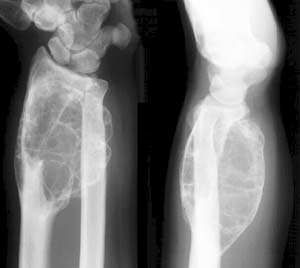

Рис. 4. Аневризматическая костная киста локтевой кости. Вздутие и ячеистость структуры кости делуют рентгенкартину похожей на гигантоклеточную опухоль.